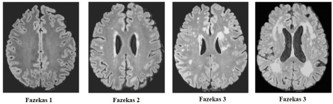

Participants were evaluated following a one-month period without the use of sedative medications (e.g., benzodiazepines), which are commonly prescribed to older individuals. All participants underwent 1,5 tesla MRI scans. The MRI protocol consisted of axial T1-weighted spin-echo images, axial, dual T2weighted Turbo spin-echo images and coronal fluid-attenuated inversion (FLAIR) images. For each image series, 20 slices covering the entire brain were obtained. White Matter hyperintensities were rated according to the Fazekas scale [11]. This is a scale of WMLs burden according to the lesions load (0: none or a single punctate lesion; 1: multiple punctate lesions=mild; 2: early confluence of lesions=moderate; 3: large confluent lesions=severe). WMLs were evaluated by lobe location, number and size. Automated quantification methods of to assess WMLs are rapidly evolving. This classification was proposed by Fazekas et al. in 1987 and at the time of writing (late 2016) it remains the most widely used system for describing white matter disease severity in publications. It is not generally used in clinical practice, with terms such as ‘mild’, ‘moderate’ and ‘severe’ being favored. Therefore, and should make it is easier to apply fine quantitative criteria for the sub-classification WMLs based on the anatomical and pathological criteria of WMLs, that comprises five areas, which supported a core region hypothesis in the central vestibular circuit: a) Subcortical area: prefrontal cortex frontal lobe, premotor cortex, frontal eye fields; b) deep periventricular; c) basal ganglia semioval center, corona radiata, caudate nucleus, globus pallidus, lentiform nucleus, thalamus, external capsule; d) parieto-insular vestibular cortex , retroinsular cortex, posterior insula, inferior parietal lobule, intraparietal sulcus, central sulcus; e) limbic system, cingulate anterior dorsal, hippocampus, amygdala, ipothalamic.

V-HIT results are outlined in Table 2. The estimates of peak location result from analysis of several neuroimaging of the WMLs, which can be subdivided in five major areas: a) subcortical area: frontal lobe, prefrontal cortex (34,6%); b) deep periventricular (34,6%); c) parieto-insular vestibular cortex (22,4%); d) basal ganglia: semioval center (22,4%), corona radiata (20,4%), caudate nucleus (6,1%), putamen (6,1%), globus pallidus (6,1%); e) thalamus (8,1%). By classification, we aim to make WMLs finding more relevant functionally. The Tab. III shows the classification and correlation between WMLs and central vestibular circuit. The Tab. IV, shows the Fazekas-scale provides an overall impression of the presence of WMH in the entire brain. On MRI, white matter hyperintensities (WMH) and lacunes both of which are frequently observed in the elderly are generally viewed as evidence of small vessel disease. It is best scored on transverse FLAIR or T2-weighted images (Figure 1). As expected, age was strongly associated with WMLs. Furthermore, sex, arterial hypertension, and diabetes were significantly associated with Fazekas scale (see Table 4. Demographic and clinical characteristics of the group as defined by amount of white matter hyperintensities.), which was not the case for hypercholesterolemia. The Table 5 illustrates the clinical characteristic of prespyvestibulopathy symptoms associated with Fazekas scale: postural imbalance (91,6%) and gait disturbance (83,3%) are associated with Fazekas 1 (focal lesion), while the chronic dizziness (79%) are associated Fazekas 2 (early confluent), finally the recurrent falls (10,4%) associated with Fazekas 3 (widespread changes in white matter). The data were also correlated of the v-HIT test with Fazekas scale: 41,6% (Fazekas 1), 47,9% (Fazekas 2) and 10,4% (Fazekas 3). Performance in v-HIT and results of the statistical analysis post hoc comparisons are illustrated in Tab. V. Fazekas groups 1 significantly in postural imbalance (91,6%) and gait disturbance (83,3%), while chronic dizziness (79%) is associated with Fazekas 2. Interestingly, only 5 patients had recurrent falls, all are related to the Fazekas 3 group.